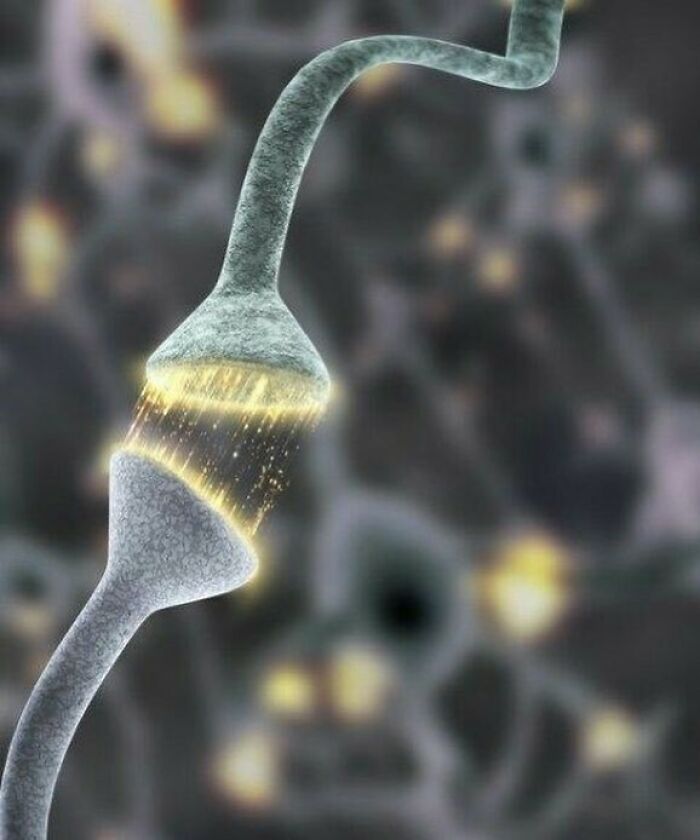

Synapse, the junction between two neurons

I don't think this is a "medical photo" so much as a computer rendering